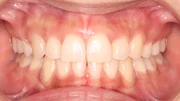

難しいケース1.抜歯症例

上下のガタガタが著しく八重歯が目立ち、見た目も歯磨きもしにくいという悩みを持った患者さま。4本の小臼歯抜歯を行い、17ヶ月という治療期間を経て、かみ合わせとスマイル時の見た目が改善しました。